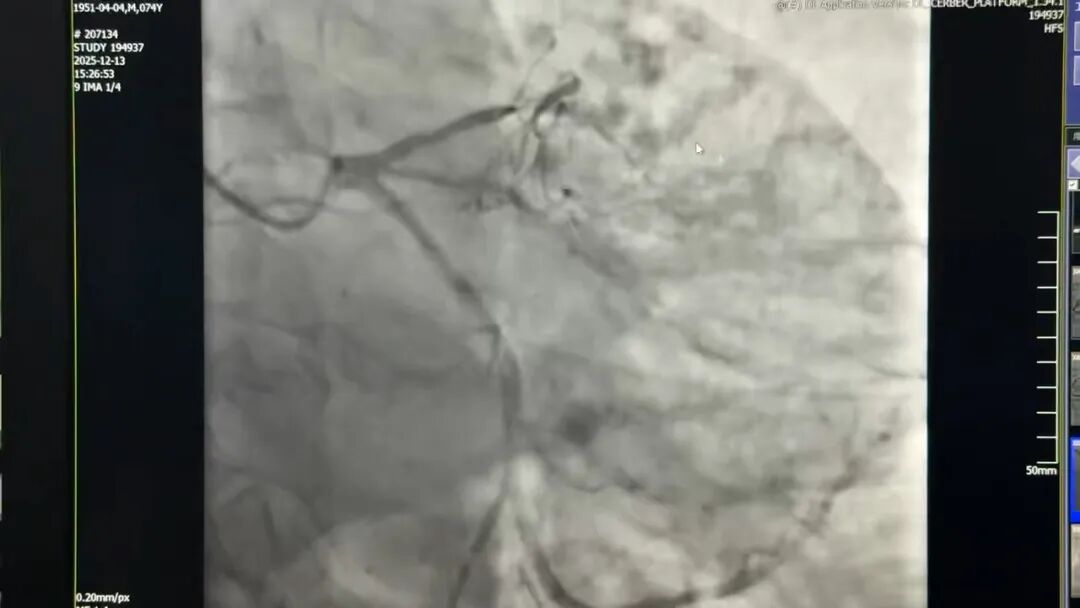

杨宏辉主任接诊后,看着患者冠脉造影视频,眉头紧锁。如果常规正向开通技术,导丝刚碰到钙化斑块就“原地打转”;如果尝试逆向路径,又被复杂的血管解剖结构死死挡住,手术难度直接拉满到“天花板级”。

专家们严密配合、精准操作,先后闯过精准旋磨、导丝通过、支架输送三个关键环节。当最后一枚支架精准释放,血管造影画面上,原本堵塞的血管瞬间“满血复活”,鲜红的血流顺畅通过,手术室里压抑的气氛瞬间消散。